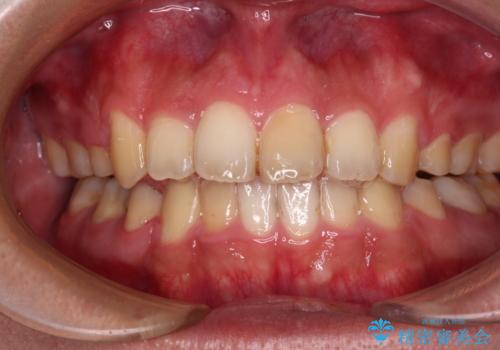

下顎骨が左側に変位しているため、正中が合わないことは予想できましたが、歯列が整った後も咬み合わせが安定せず、咬み合わせを落ち着かせるために1年以上の期間を要しました。

噛みにくさの改善に時間がかかってしまうことがインビザラインの欠点の1つといえます。